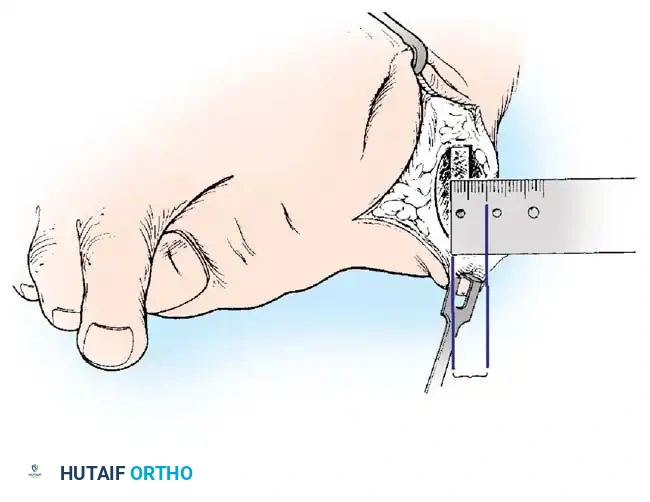

Fig. 78-8 A, Determination of position of articular surface of metatarsal head in relation to longitudinal axis of fi rst metatarsal. B, Measurement of distal metatarsal articular angle at time of surgery. Markings are at medial and lateral margins of articular surface of fi rst metatarsal head and longitudinal axis of fi rst metatarsal shaft. metatarseum between the bases of the fi rst and second metatarsals might preclude the effectiveness of a soft-tissue procedure alone to provide suffi cient correction of the increased intermetatarsal angle. Likewise, accessory sesamoids and prominent ungual tuberosities at the interphalangeal joint contribute to a painful callus at the tibial side of this joint. An os tibialis externum frequently is associated with excessive hallux valgus interphalangeus. Varus of the fi rst metatarsal might be a signifi cant part of the overall deformity of the foot even with an intermetatarsal angle of less than 10 degrees. Metatarsus varus with a relatively small hallux valgus angle (15 to 20 degrees) may produce signifi cant deformity even though the angles are not excessive. The usefulness of computer-assisted compared with manual measurement of the intermetatarsal angle, hallux valgus angle, and distal metatarsal articular angle is still uncertain. Both methods have closer interobserver and intraobserver correlation in measurement of the intermetatarsal angle and hallux valgus angle than in measurement of the distal metatarsal articular angle. The reliability of either method has such a wide range (5 degrees), however, that measurements of these angles, although useful as a guide, do not provide a completely reliable indication of the magnitude of deformity. Condon et al. suggested that the reliability of the intermetatarsal angle can be improved by careful technique and by making the measurements at least twice and averaging them. Schneider et al. reported two methods of determining angular measurements based on distinctly different reference points: (1) a longitudinal axis of the fi rst metatarsal using middiaphyseal reference points, and (2) a center-head technique using a center head (center of the articular surface) and center base

Fig. 78-11 Location of reference points for fi rst and second metatarsals are between 1 and 2 cm from distal articular surface and proximal articular surface of each metatarsal. Because of shorter length of hallux, reference points are placed between 0.5 and 1 cm from proximal and distal articular surface of proximal phalanx. (From Coughlin MJ, Saltzman CL, Nunley JA II: Angular measurements in the evaluation of hallux valgus deformities: a report of the ad hoc committee of the American Orthopaedic Foot and Ankle Society on angular measurements, Foot Ankle Int 23:68, 2002.) support and the medial capsule acting as a spring on stretch. Osteotomy usually is indicated in patients with this medial wedged opening of the joint. If a fi rm forefoot wrap reduces the intermetatarsal angle to a normal value and decreases the hallux valgus angle, however, while congruously rotating the base of the fi rst metatarsal on the medial cuneiform without levering the joint open medially, the McBride procedure can correct the deformity. Correction is improved by excision of the fi bular (lateral) sesamoid because the adductor hallucis and lateral head of the fl exor hallucis brevis are released, markedly reducing the valgus moment at the fi rst metatarsophalangeal joint. In addition, the pull of the fi bular sesamoid on the fl exor hallucis longus through its tendon sheath and pulley system is prevented, reducing another important valgus-producing force on the hallux at the metatarsophalangeal joint. If the fi bular sesamoid is excised, the medial capsule should be repaired with the hallux held in 10 to 15 degrees of valgus. This position must be maintained by a postoperative dressing for 3 or 4 weeks.